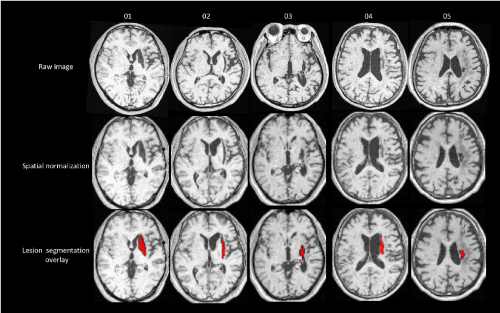

The overall distribution of lesions in our patients is described in Figure 2a. We show exactly which voxels were included in VLSM (Figure 2b). We scaled from 10 to 50 patients.

Figure 2. Voxel-based lesion-symptom mapping (VLSM)

(a) Overlap lesion plot from 50 stroke patients. The number of overlapping lesions is coded with colors ranging from dark blue (n = 1) to light red (n = 50 patients). (b) Only voxels affected in at least 10 patients were included in the VLSM analysis. We showed exactly which voxels were included in the analysis. We scaled from 10 to 50 patients. (c) All voxels below t = −3.8 were significant at P = 0.05 (FWE correction). (d) All voxels above t = 3.7 were significant at P = 0.05 (FWE correction). (e) All voxels above t = 3.6 were significant at P = 0.05 (false discovery rate correction). VLSM demonstrates that lesions on the thalamus are associated with motor function. (f) All voxels below t = –3.8 were significant at P = 0.05 (false discovery rate correction). VLSM demonstrates that lesions on the thalamus are associated with motor function.

Stroke injury site

VLSM analyses revealed that pre-intervention WMFT scores were significantly associated with damage to the thalamus and corticospinal tract (FWE P < 0.05, Figure 2c). Further, pre-intervention FMA scores were also significantly associated with damage to the thalamus and corticospinal tract (FWE P < 0.05, Figure 2d). The degree of improvement in WMFT and FMA scores was also associated with lesions on a network centered in the thalamus areas and corticospinal tract (false discovery rate P < 0.05, Figure 2e, Figure 2f).